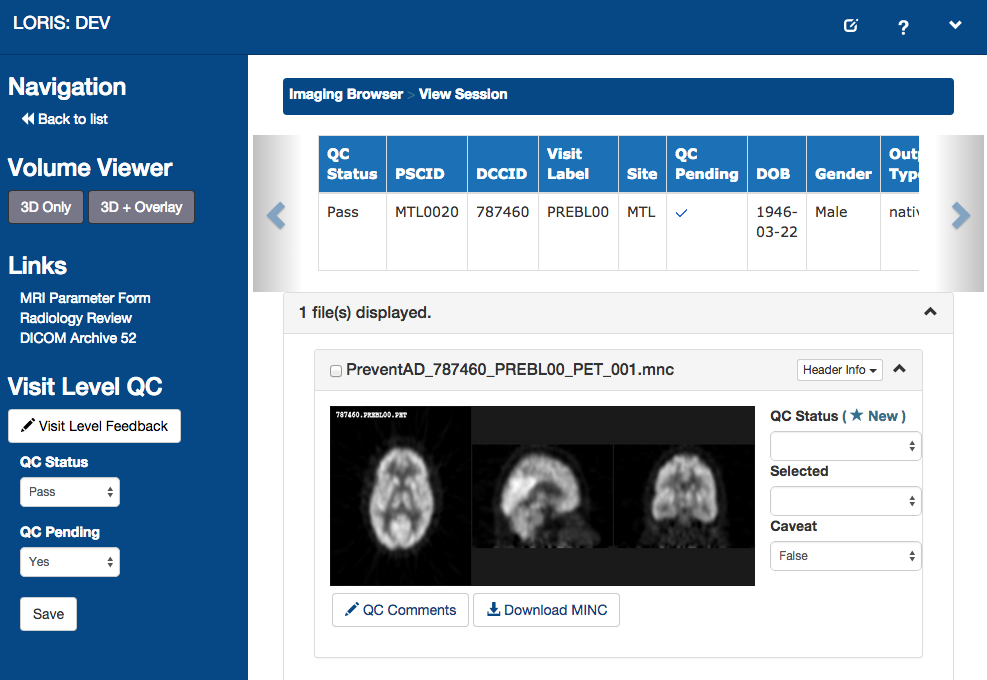

Imaging Data

1. Acquisition & Storage

2. Visualisation:

Imaging Browser, BrainBrowser3. Quality Control:

Radiological Review Module, DCC MRIData Querying

Imaging Browser

Imaging Quality Control

Automated PET recognition

Automated PET recognition